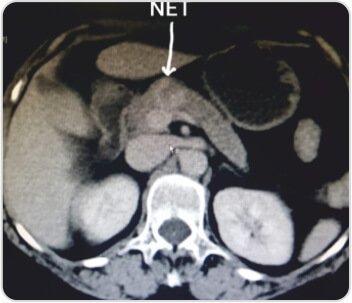

CECT abdomen shows a 2.5 cm mass in the neck of the pancreas. Whole body PET-CT shows no other site of disease. EUS guided FNAC gives a diagnosis of neuroendocrine tumor of pancreas. Patient underwent central pancreatectomy and Roux-en-y pancreaticojejunostomy. Procedure was uneventful and the patient was discharged after 5 days.